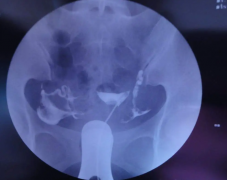

盆腔检查室;超声;激素检测;国家一级手术室和IVF实验室;人工授精实验室;精液分析的诊断;盐水灌注超声检查;诊断性腹腔镜检查;子宫输卵管诊断等等。